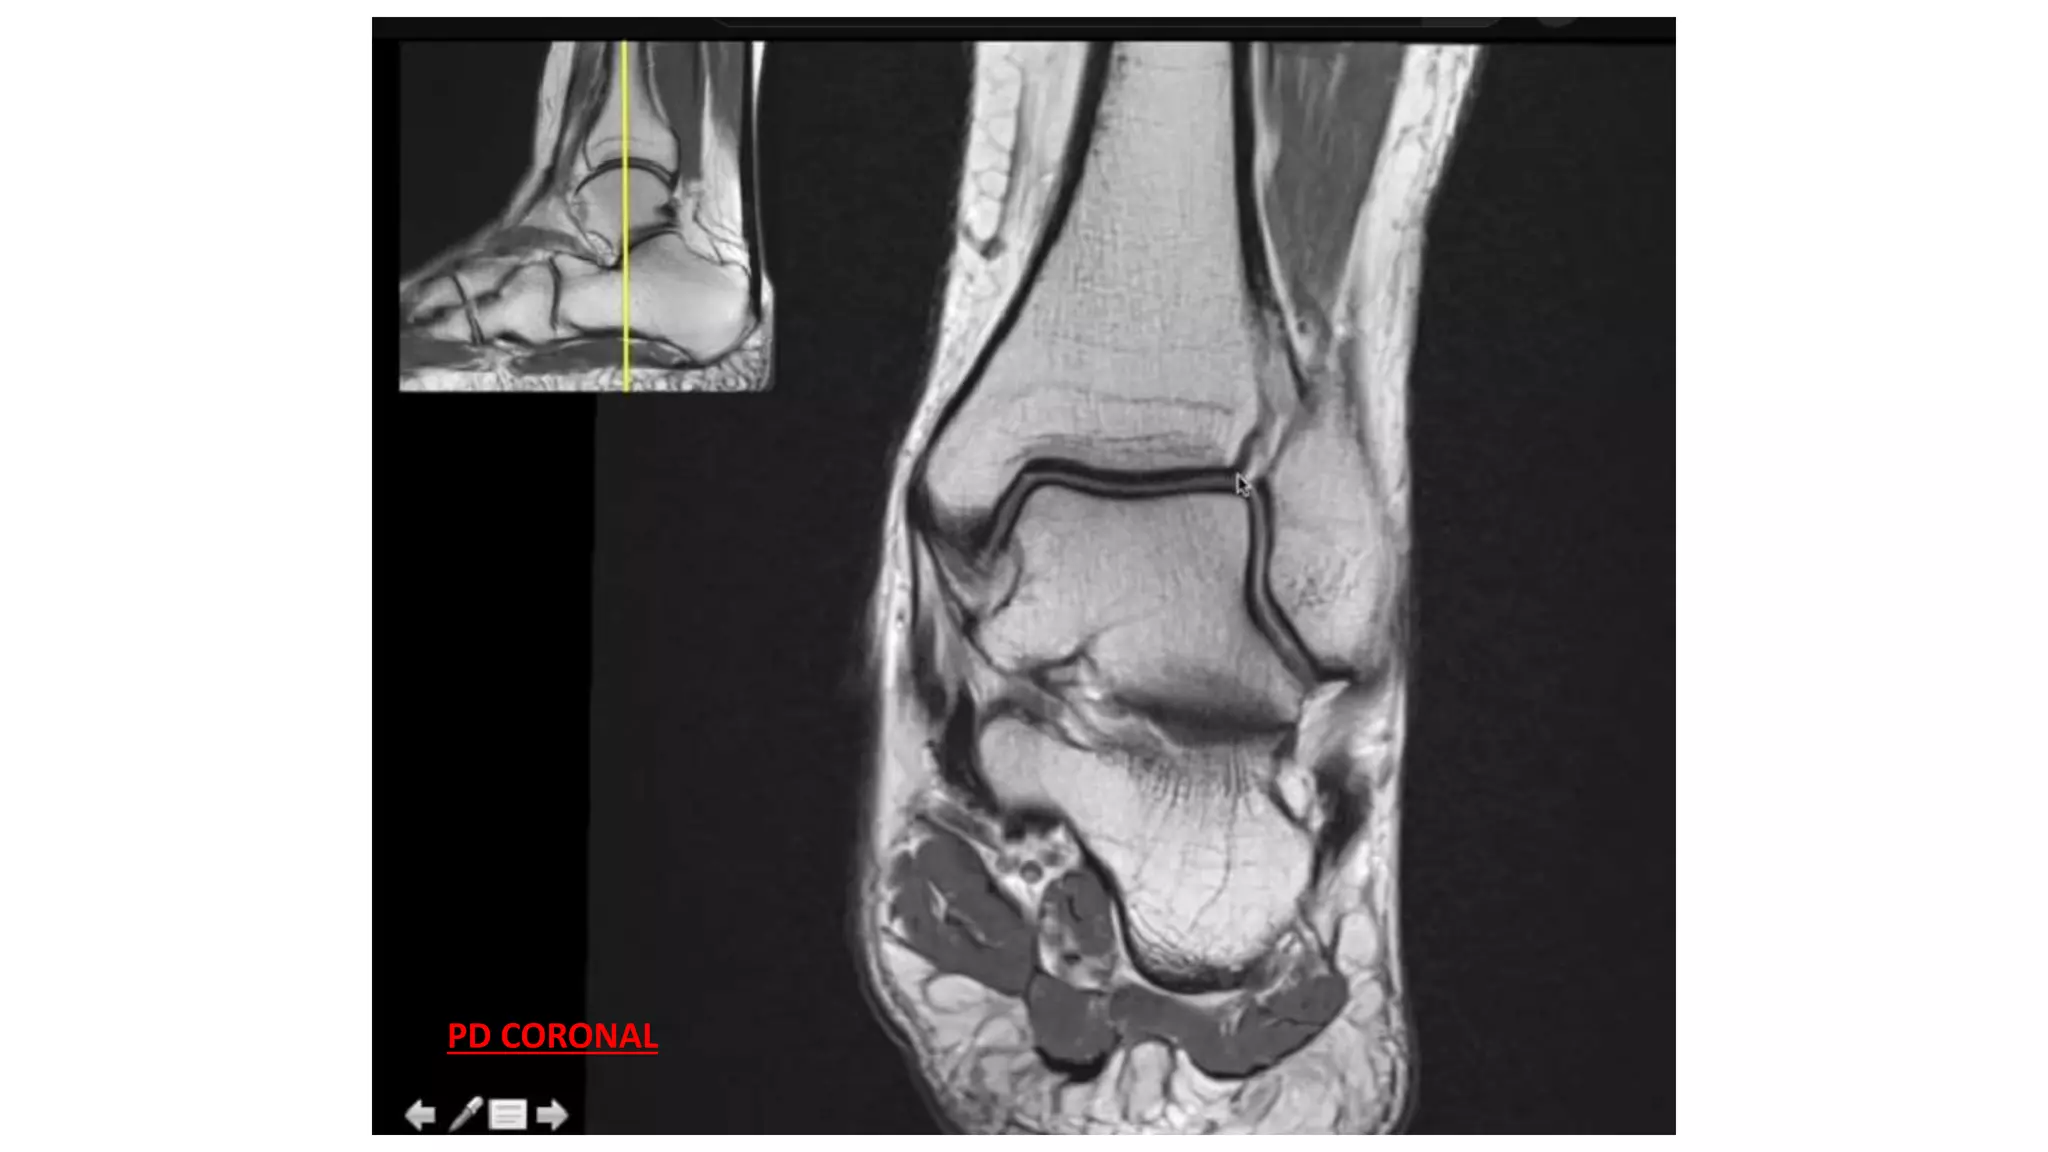

This MRI ankle report describes the anatomy of the ankle, including ligaments such as the anterior and posterior tibiofibular ligaments, syndesmosis ligaments, deltoid ligament, and calcaneofibular ligament. It outlines the tendons in the anterior, lateral, medial, and posterior compartments, including the tibialis posterior, peroneus, flexor hallucis longus, and Achilles tendons. The sinus tarsi is also noted.